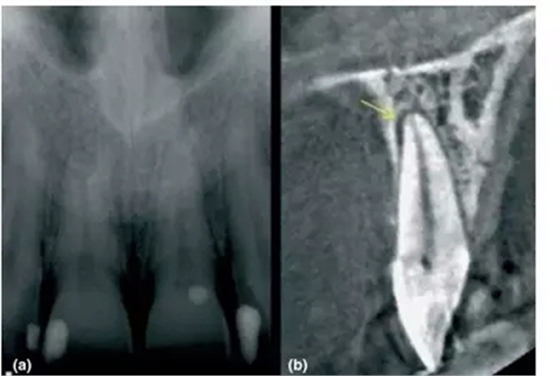

a- 11和21根尖影像無異常,但患者主訴該區(qū)有間歇的鈍痛

b-CBCT顯示21腭側(cè)有透射影,根管治療后患者癥狀消失

前文中已經(jīng)討論了能顯示在傳統(tǒng)X片上根尖周暗影,其范圍一定侵犯到皮質(zhì)骨。然而CBCT卻能精準(zhǔn)探測只局限于松質(zhì)骨中的病損,讓臨床醫(yī)生能早診斷、早處理,提高現(xiàn)代牙體牙髓治療的成功率。